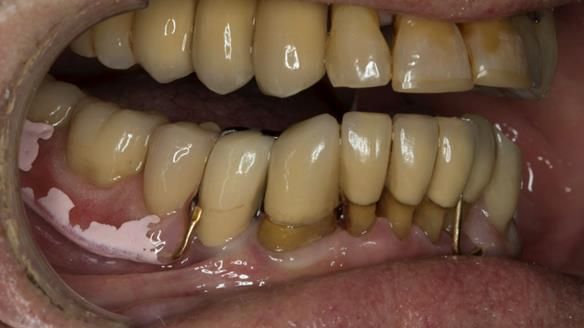

The starting point

We began with the lower jaw.

A posterior implant 47 had lost integration and was infected. This was removed.

Ken did not want further implant surgery.

Instead, we made a Scandinavian-style, metal-based lower RPD.

It was made promptly, then relined gradually over the following year

to optimise fit, comfort, and support.